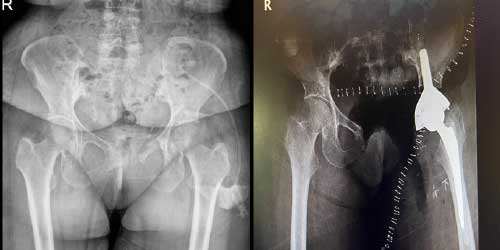

66 yaş kadın hastada proksimal femur kondrosarkomu nüks etti. Internal hemipelvektomi ve antibiyotikli spacer ile rekonstrüksiyon başarıyla uygulandı.